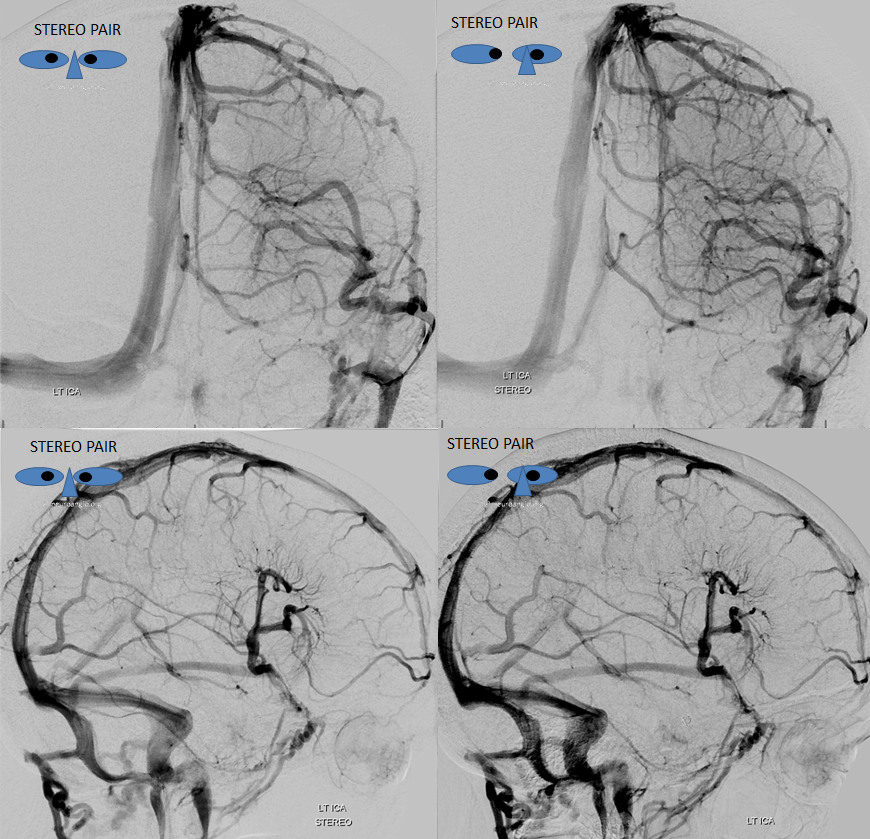

Sagittal Sinus Thrombosis — collaterals.

All of the above anatomic knowledge can become very useful in evaluation of venous thrombosis. Numerous collateral pathways develop in this setting attempting to compensate for the loss. The most dramatic cases usually involve the largest channel — the superior sagittal sinus. In this case, a man presented with what initially was thought to be vasculitis-related brain hemorrhage. Subsequent workup led to an angiogram, where sagittal sinus thrombosis with extensive trans-cerebral and trans-osseous emissary vein collateral channels was seen. In retrospect, these findings were present on the patient’s earlier contrast MRI. “Venovibe” or other contrast-enhanced MR venograms can very sensitive, particularly when interpreted with the appropriate index of suspicion. Noncontrast 2-D time of flight MRV I consider to be next to useless as a problem-solving technique. Any thin-slice postcontrast T1 study is vastly superior.